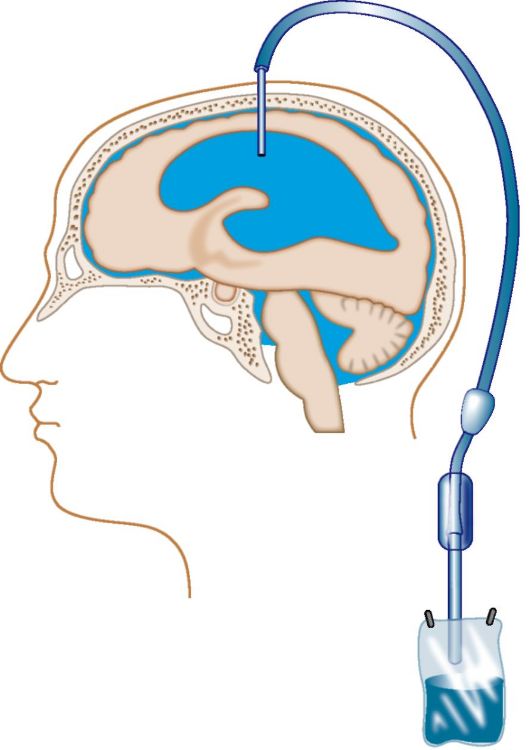

Иногда при открытой гидроцефалии проявляется тенденция к стабилизации ликвородинамики, и ребенок с увеличенным мозговым черепом в дальнейшем сохраняет жизнеспособность и развивается более или менее удовлетворительно. При выявлении причины внутричерепной гипертензии и гидроцефалии следует обсудить возможность их ликвидации. Вопрос о такой возможности обычно решается неврологами совместно с нейрохирургами. В таких случаях радикальным может быть нейрохирургическое лечение, например тотальное удаление некоторых доброкачественных внутричерепных новообразований или субдуральной гематомы (см. главу 33). В других случаях консервативное или хирургическое лечение может обусловить улучшение состояния, стойкую ремиссию в течение заболевания, хотя в перспективе возможно обострение, требующее нового курса консервативного лечения или повторного оперативного вмешательства, как это бывает после частичного удаления доброкачественной глиомы, например кис- тозной астроцитомы полушария мозжечка. Если оказать радикальную помощь больному или обеспечить хотя бы временное улучшение в состоянии больного путем лечения основного заболевания нет возможности, то в некоторых случаях можно проводить паллиативные операции, в частности резекционную краниотомию с целью декомпрессии полости черепа. Если патологический очаг не может быть удален и при этом он перекрывает ликворные пути, вызывая окклюзионную гидроцефалию, возможна паллиативная операция - создание обходного пути циркуляции ЦСЖ. При ведущих к окклюзионной гидроцефалии патологических очагах на уровне водопровода мозга или IV желудочка мозга можно создать переток СМЖ из III желудочка мозга в ликворные цистерны основания черепа путем перфорации передней или задней стенки этого желудочка (операция Стукея-Скарфа, 1936). Чаще, однако, в таких случаях проводится вентрикулоцистерностомия по Торкильдсену, в процессе которой обеспечивается отток ЦСЖ из заднего рога бокового желудочка мозга в мозжечково-мозговую, или большую, ликворную цистерну, реже проводится вентрикуло-перитонеальное шунтирование (рис. 20.3). При открытой гидроцефалии иногда устанавливается люмбоперитонеальный шунт (рис. 20.4).

Рис. 20.3. Вентрикулоцистернальное дренирование по Торкильдсену.

Рис. 20.4. Наружное дренирование желудочков мозга.